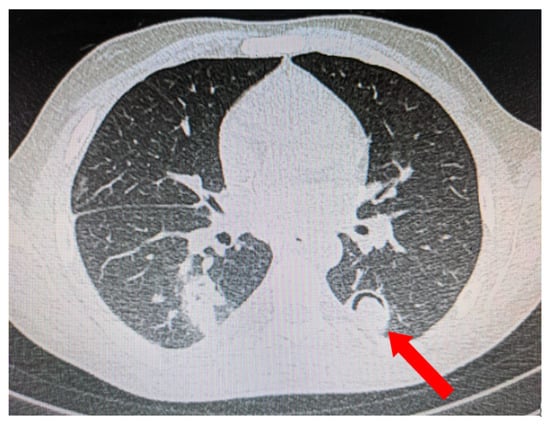

5.1. Role of Diagnostic Imaging

Diagnostic imaging is vital for early detection of invasive mucormycosis in patients with clinical suspicion. Certain distinguishing features of the lung parenchyma on a CT scan of the chest in patients with PM include multiple pulmonary nodules, often pleural-based, presence of lung cavitations and effusions (Figure 1, Figure 2, Figure 3 and Figure 4) [23]. The ‘reverse halo sign’ (central ground glass opacity surrounded by dense consolidation) is highly appreciated, mainly in neutropenic leukemic hosts. In a recent systematic review of CT findings in 16 patients with proven CAPM, consolidation and cavitation were seen in 11 (69%) patients, pleural effusion in 7 (47%), pneumothorax and nodules in 3 (19%) and ‘reverse halo sign’ and pulmonary embolism was seen in 2 (13%) patients [24]. Previously, Nam et al. reported that in hematologic patients, while consolidation and nodules are seen earlier in the disease process, central necrosis, cavitation and the air crescent sign are late findings [25]. This would suggest that CAPM is either under-diagnosed due to lack of differentiation from other fungal, including aspergillosis or bacterial pneumonias, or is diagnosed much later in the illness.

Figure 4. Pleural-based consolidation with cavity and a radio-opaque shadow within the cavity leading to formation of ‘air crescent’ (red arrow).